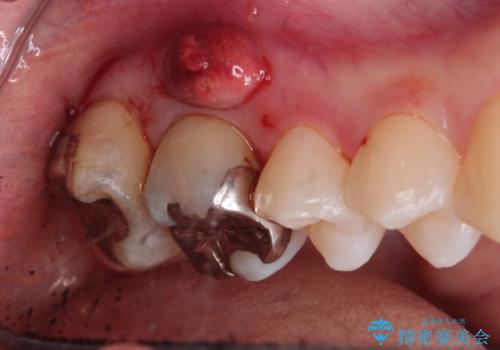

- 右上の歯茎が腫れてきたとのことで来院されました。

右上6番目の歯の位置に腫脹があり、膿も出ている状態でした。

レントゲンを撮影すると、根の先端から膿が排出されていることがわかりました。

根の神経が細菌に感染するとこのように、膿の出口ができることがあります。

その場合は、根の中の治療(根管治療)が必要になります。